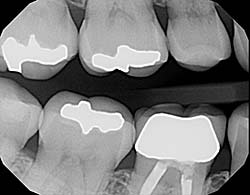

Using the most advanced dental technology possible is just as important as staying up-to-date on the latest treatment techniques. Because our practice is dedicated to providing you with the safest and most convenient treatment options available, we utilize advanced digital X-ray technology in our office.

Digital X-rays provide several advanced imaging options, designed to save time, provide clearer dental photos, and expose patients to less radiation than with traditional X-ray technology.